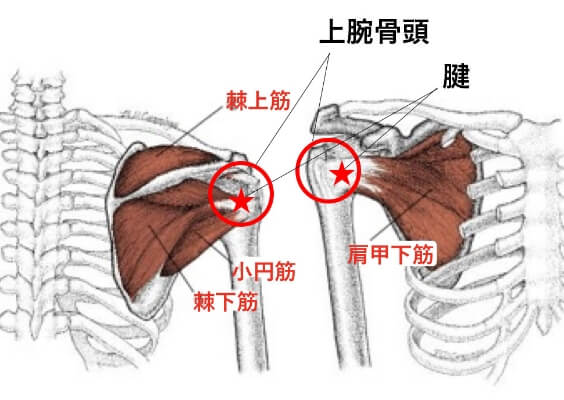

2.腱板損傷

腱板とは、肩の中にある棘上筋、棘下筋、小円筋、肩甲下筋という4つの筋肉の腱の複合体を言います。スポーツでこの部位を負傷することは多く、腱板損傷とは、肩にある上腕骨頭に付着している腱が骨頭から剥がれたり、破れたりする損傷のことを言います。投球動作の他、ラケット競技、あるいは転倒した際に肩から落ちるなどの外傷が、その原因として挙げられます。

痛みで腕が挙がらない。夜、痛みで目が覚める。腕を下ろす時にも痛みが走る。痛くなったほうの肩を下にして寝られないなどの症状が現れます。